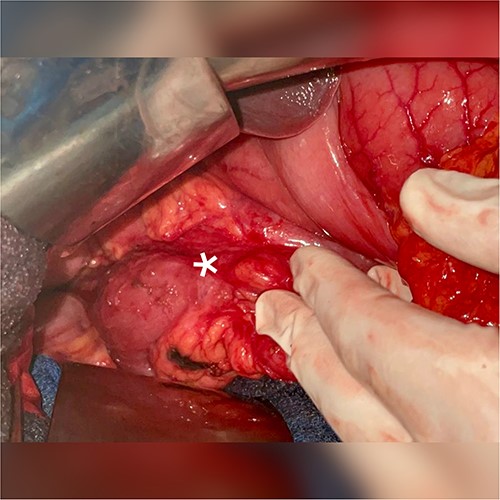

A 51-year-old patient with no significant medical history. He was admitted to the emergency department with abdominal distension, persistent vomiting, intolerance to solid foods, he could consume only small amounts of liquid. Clinical examination of the abdomen revealed diffuse tenderness in all quadrants, accompanied by severe abdominal distension. Prior to his consultation at our institution, he had undergone oesophagogastroduodenoscopy, revealing a dilated stomach and narrowing of the pyloric ring. Biopsies revealed the presence of H. pylori and S. ventriculi. (Fig. 1). He was put on conservative treatment for a duration of ~4 weeks, but no significant improvement was noted. On admission to our clinic, he underwent a computed tomography (CT) scan of the abdomen (Fig. 2), which revealed marked dilatation of the stomach, as well as an upright arrangement of the entire jejunal coves, suggesting the presence of a high occlusion due to a right anterior para-duodenal internal hernia. While a more comprehensive non-operative management approach could have been contemplated in the absence of hernia-related concerns, the clinical deterioration and the refractory nature of symptoms to medical therapy served to underscore the appropriateness of the surgical approach. During surgery, the hypothesis of a para-duodenal internal hernia was ruled out after a duodeno-pancreatic detachment using the KOCHER maneuver, thus facilitating exposure of the entire duodenum and also allowing individualization of the transition zone located at the level of the pylorus (Fig. 3), thus justifying the performance of gastroenteric anastomosis (Fig. 4). Post-operatively, the diet was progressively advanced and well tolerated. On discharge, the patient was in satisfactory condition.

Individualization of the transition zone located at the level of the pylorus.